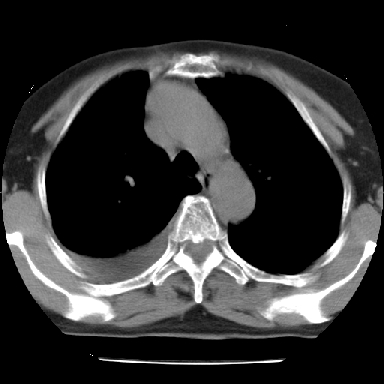

以下是引用苯小孩在2007-4-13 16:20:00的发言:[br]1、右下肺中央型肺癌并阻塞性肺不张、肺内转移、胸椎右侧附件亦有转移<横断层面第8层>.[br]2、右侧胸腔积液.

以下是引用swyyy2007在2007-4-13 15:31:00的发言:[br]右肺门下区肿块,右肺下叶支气管阻塞,右肺下叶不张,右侧大量胸腔积液,右肺中叶见结节状高密度影,边缘清,纵隔内见肿大淋巴结。首先考虑右下肺中心型肺癌伴右肺下叶不张、中叶、纵隔淋巴结转移。右侧胸腔积液。